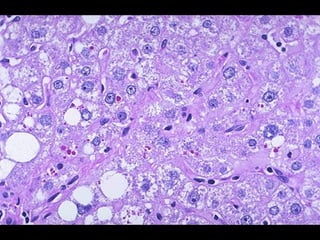

GLUCÓGENO •- Se observaen pacientes con anomalías en el metabolismo de la glucosa o el glucógeno.- •- Las masas de glucógenos aparecen en forma de vacuolas claras dentro del citoplasma. Se evidencian mejor con la coloración de PAS y dejan de observarse al utilizarse el PAS + diastasa.- •- Los ejemplos típicos incluyen a la diabetes mellitus y las enfermedades por almacenamiento de glucógeno